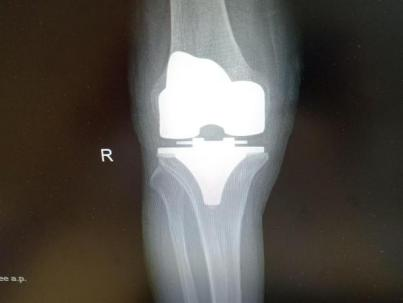

4月23日,贵州航天医院第58次晨读会由我院骨科副主任医师张艳金作学术交流,他以“加速康复指导下的快速手术”为题,详细讲解了老年股骨粗隆间骨折与儿童四肢骨折的临床诊疗难点,结合加速康复外科(ERAS)核心理念,重点阐述了ERAS理念在两大人群中的创新实践,实现患者入院后6至24小时内即可接受手术治疗。针对老年髋部骨折患者,提出通过多学科协作(MDT)与微创手术优化围术期管理,在确保安全前提下缩短术前等待时间,实施精准化麻醉及术后康复方案,可有效降低并发症发生率、改善患者生活质量和预后效果。在儿童骨折领域,强调微创术式与心理干预并行的双轨策略,既减少手术创伤对骨骼发育的影响,同时关注患儿心理疏导,实现生理功能与心理健康同步康复。并通过典型案例的影像学资料与随访数据,直观展示了ERAS理念指导下骨科治疗模式的创新成果。 贵州航天医院骨科 专家简介 赵学平 中共党员,骨科党支部书记、主任,主任医师 临床擅长:从事骨科临床工作30余年,对骨科常见疾病的诊治具有丰富的临床经验。 世界中医药联合会脊柱康复专业委员会常务理事,中华中医药学会整脊分会常务委员,中国中西医结合学会骨伤科分会肢体矫形功能重建与康复专家委员会常务委员,中国研究性医院学会骨科创新与转换专业委员会关节外科学组保髋工作委员会常委,中国康复技术转化及发展促进会骨外科与康复技术转化专业委员会常务委员,泛珠三角区域运动医学联盟(PPRD-SMA)理事会常务理事,中国研究型医院学会运动医学专业委员会委员,贵州省中医药学会整脊分会副主任委员,贵州省中西医结合学会银质针专业委员会副主任委员,贵州省康复医学会骨与关节专业委员会常务委员,贵州省人民医院骨科专科联盟常务理事,贵州省康复医学会骨内科专业委员会常务委员,中华医学会贵州省骨科学会委员,贵州省康复医学会脊柱脊髓专业委员会常务委员,贵州省运动医学分会委员,贵州省康复医学会骨与软组织肿瘤专业委员会委员,遵义市医学会创伤分会副主任委员,贵州省康复医学会骨内科专业委员会遵义地区分会常务委员,遵义市医疗事故鉴定、伤残鉴定、工伤鉴定、司法鉴定专家。 长期从事骨科临床研究及教学工作,在国家级、省部级杂志发表论文20余篇,SCI论文2篇,参与主编骨科专著2部,主持省部级科研项目2项,参与指导省部级、市级科研项目6项。 陈明勇 骨科副主任,副主任医师 临床擅长:从事创伤骨科工作约20年,对骨缺损、骨不连、骨肿瘤、肢体畸形等的肢体矫形重建及功能重建,慢性化脓性骨髓炎的根治治疗、糖尿病足的保肢治疗、快速康复理念(ERAS)下的老年骨折的诊治,四肢复杂骨折的诊治,四肢骨折等微创手术治疗具有丰富的临床经验。 2004年毕业于遵义医学院临床专业,曾在中国人民解放军总医院、广西医科大学第一附属医院、上海第六人民医院骨科进修。中国中西医结合学会骨伤科专业委员会横向骨搬移治疗糖尿病足及微血管网再生学组首届委员,遵义市医学会创伤分会常务委员。 瞿 辉 中共党员,骨科副主任医师 临床擅长:对骨科的常见病、关节外科、脊柱外科及运动医学疾病的诊治具有丰富的临床经验,熟练掌握骨科手术操作技术。 毕业于遵义医学院临床医学系,2005年前往广州中山大学第一附院骨显微医学部进修学习,2011年前往成都华西医院进修学习,并多次在省内外学习骨科相关知识,是中华医学会骨科分会会员。 赵兴东 骨科主任医师 临床擅长:擅长骨科的常见病及各种创伤、四肢骨折创伤修复、骨感染、手足疾病的诊治和手足体表畸形的矫形整复,熟练掌握骨科四肢骨病及创伤的手术操作技术,尤其在四肢关节复杂性损伤、手足外伤、组织缺损创面、难治创面的皮瓣修复方面及平足、高弓足矫形方面及四肢慢性疼痛诊治、康复方面具有丰富的临床经验。 硕士研究生,毕业于遵义医学院临床外科系,2015年前往山东省立医院手足外科进修学习;遵义市医学分会创伤分会第一、二届委员,遵义市手外科医学会第二委届员会常务委员;在省级及省级以上期刊发表文章9篇,参编著作2部,参与主持并完成市级课题1项,参与市级课题2项、省级课题1项。 张艳金 中共党员,骨科副主任医师 临床擅长:从事骨外科工作16年,对复合伤、多发伤的救治、四肢骨干骨折、关节周围骨折、骨肿瘤、骨髓炎等诊治具有丰富的临床经验。 中共党员,硕士研究生,2006年本科毕业于山西医科大学第二临床医学院,2011年研究生毕业于北京军区总医院;在“老年COPD患者合并髋部骨折的诊治”国际合作课题组研究两年,在老年髋部骨折的诊治方面具有丰富的经验,并发表论文6篇;主持遵义市级课题1项,承担遵义医科大学的临床教学工作,获得遵义医科大学优秀带教老师荣誉。编撰有《骨科疾病诊疗精粹》一书,开展2项新技术,编撰地方规范《务川自治县创伤骨科常见疾病诊疗规范》一书。 张俊凯 骨科副主任医师 临床擅长:从事骨科临床工作28年,对创伤骨折、骨感染、骨缺损、骨不连等外科诊治,四肢骨折的微创手术治疗,四肢复杂骨折(如关节内粉碎性骨折、多发骨折等)的损伤控制及手术治疗等具有丰富的临床经验。 1995年毕业于遵义医学院临床专业,2009年前往复旦大学附属医院骨科进修1年。 卢懿明 中共党员,骨科副主任医师 临床擅长:从事骨科工作18年,对创伤骨折、四肢骨折的微创手术治疗、四肢复杂骨折(如关节内粉碎性骨折、多发骨折等)的损伤控制及手术治疗,尤其是髋部骨折的PFNA等微创技术,踝关节骨折、膝关节周围骨折的Mipo微创技术等具有丰富的临床经验,开展了4项新技术,发明6项新型专利技术。 2005年毕业于遵义医学院临床专业,2017年,前往南方医科大学第三附属医院骨科进修半年,回院后运用Mipo技术对骨干骨折及干骺端骨折的治疗技术,同时积极开展骨盆骨折、髋臼骨折腹直肌外侧切口的应用;发表了多篇专业论文,经常参与省内外学术交流会授课,获得医院荣誉称号多个。 邬夏荣 骨科副主任医师 临床擅长:从事骨科工作16年,对四肢复杂骨折、骨肿瘤的诊治,尤其是足踝创伤、慢性踝关节损伤、平足症等诊疗具有丰富的临床经验。 2006年毕业于遵义医科大学临床医学专业,曾在陆军军医大学西南医院进修学习,发表多篇骨科学术论文。 余德怀 中共党员,骨科副主任医师 临床擅长:从事骨科工作10余年,对运动医学、骨关节、脊柱外科常见病、多发病的诊治具有丰富的临床经验。 硕士研究生,2011年毕业于遵义医学院临床医学专业,曾前往遵义医科大学附属医院运动医学专业进修学习;是贵州省医学会运动医学分会青年委员,西部关节镜联盟委员;发表多篇骨科学术论文。 冯 乾 骨科副主任医师 临床擅长:从事骨科工作近20年,熟练掌握骨科多发病及常见病的诊治,尤其对脊柱退变性疾病的诊断及治疗具有丰富的临床经验,主要研究脊柱微创相关治疗方式,能熟练开展椎间孔镜及UBE。 曾前往北京大学第三医院进修学习疼痛及椎间孔镜、首都医科大学友谊医院专业进修脊柱内镜;是贵州省康复医学会第三届脊柱脊髓专业委员会委员;发明专利3项、发表脊柱外科专业论文多篇。 赵小锋 中共党员,骨科副主任医师 临床擅长:从事骨科临床工作11年,对骨科常见病、多发病诊疗有较为丰富的临床经验,擅长脊柱相关疾病诊断及治疗,尤其是颈、腰、腿疼痛疾病诊断及治疗,擅长胸腰椎骨折微创经皮穿刺内固定术、经皮穿刺椎体成形术、经皮穿刺脊柱内镜下腰椎间盘摘除术、单纯开创腰椎间盘摘除术、腰椎滑脱复位椎间植骨椎融合内固定术、腰椎管狭窄减压融合内固定术及人工髋、膝关节置换术等。 2012年毕业于遵义医学院外科学专业硕士研究生,2019年参加“遵义市115医学人才精英计划”于上海交通大学第一附属医院培训学习,2023年于北京大学第三人民医院脊柱外科进修学习,曾获得遵义市优秀医师荣誉称号。 遵义市手外科第一届委员,遵义市医学会创伤分会第一届委员,遵义市医学会创伤分会第二届委员,贵州省康复医学会第三届脊柱脊髓专业会委员,遵义市医学会烧伤与整形外科学分会委员,发表论文5篇,其中国家级核心期刊1篇,SCI论文1篇,主持市级课题1项并结题,参与市级课题2项。 贵州航天医院骨科 简介 基本情况 贵州航天医院骨科组建于20世纪60年代,前身是以创伤和断肢(断指)再植闻名于世的上海市第六人民医院骨科,中国断肢(断指)再植的奠基者、中科院院士陈仲伟等著名专家、学者多次莅临科室指导医疗、教学,是贵州省最早拥有专业骨科技术科室之一,在70年代开展了贵州省首例断肢(断指)再植手术。组建50余年来,诊治患者已逾百万,挽救了无数的伤病员,成为了保障遵义地区人民群众健康的重要支撑。 经过几代人的不懈努力,今天的骨科,已由创伤骨科发展至骨病、骨肿瘤、骨结核等领域,现有脊柱外科、关节外科、四肢创伤、手足外科四个亚专科,成为了集医疗、教学、科研于一体的综合学科,是贵州省临床重点专科、遵义市临床重点专科、遵义市骨科临床医学中心、遵义市基层骨科专科联盟理事长单位。 科室目前开放床位110张,共有医护人员50余人,副高级以上专家18人,硕士研究生15人。拥有一流骨科医疗设备多台,每年不定期选派优秀技术骨干到全国各大知名医学院校进修、学习、参观、交流,并邀请国内、国外知名专家教授来院进行交流、指导,通过不断引进国内外先进的诊疗技术,科室医疗技术水平稳步提升,为广大人民群众提供了优质的医疗服务。 专科特色 骨一科 (一)骨缺损、骨不连的肢体与功能重建 胫骨横向骨搬移技术治疗糖尿病足: (二)慢性骨髓炎的根治治疗 (三)肢体缺血性疾病如糖尿病足、脉管炎的保肢治疗 (四)皮瓣修复 (五)复杂创伤的治疗 (六)老年髋部骨折及小儿骨折快速手术 老年髋部骨折: 骨二科 (一)胸腰椎骨折微创经皮椎弓根螺钉固定术 (二)老年性骨质疏松性患者腰椎滑脱脊柱内固定术(骨水泥螺钉) (三)V形双通道脊柱内镜技术(VBE)腰椎融合术治疗腰椎退行性疾病 (四)老年性骨质疏松性骨折(PVP/PKP)术 (五)人工髋关节置换术 (六)双侧股骨头坏死人工全髋关节置换 (七)右侧全髋置换术后假体周围骨折翻修 (八)人工膝关节置换术 (九)人工膝关节假体松动翻修 (十)关节镜技术 传统手术切口 关节镜技术切口 诊疗范围 骨一科 1.四肢创伤、矫形。 2.手、足踝外科。 骨二科 end